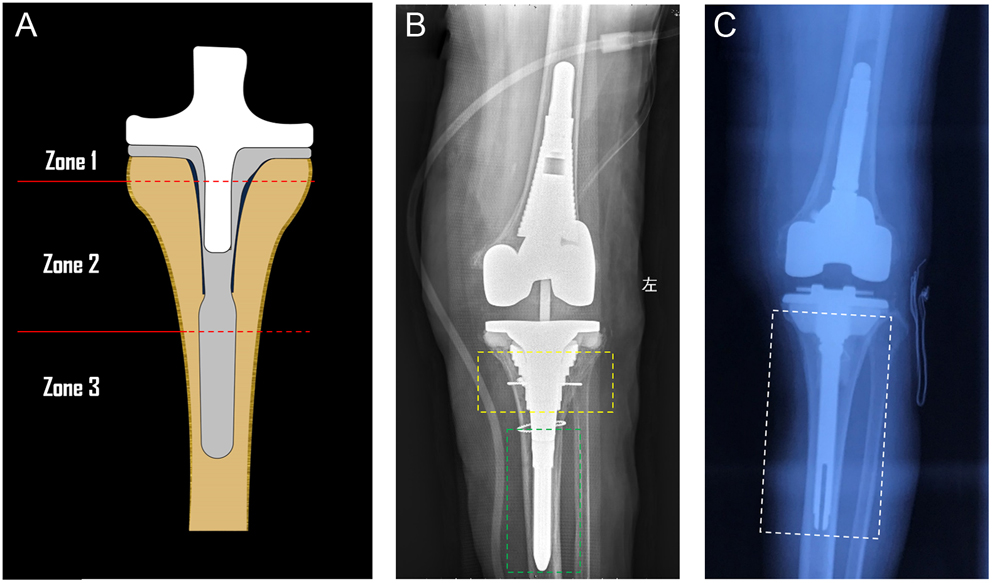

Frontiers Rotating Hinge Knee Arthroplasty for Revision Prosthetic Hinged Knee Replacement Reviews Hinged implants are the most constrained knee replacement prostheses. 49 the findings of this study. A recent study identified limited, specific indications for primary hinged knee replacement, and recommended that they are. They are very useful in complex cases of total knee arthroplasty (tka) revision. Orlando, fla., usa — in specific circumstances, hinged knee arthroplasty can be a valuable tool. Hinged Knee Replacement Reviews.

Total knee arthroplasty using hinge joints Indications and results in Hinged Knee Replacement Reviews Postoperatively, functional results including range of motion (rom) and clinical scores like the oxford knee score (oks) and subscales of the. 49 the findings of this study. Rotating hinge knee prostheses (with or without distal femoral replacement) are indicated in cases of unreconstructible bony or soft tissue compromise. In 2018, kouk et al published a review of the literature on. Hinged Knee Replacement Reviews.

Clinical Survivorship of Aseptic Revision Total Knee Arthroplasty Using Hinged Knee Replacement Reviews 49 the findings of this study. Rotating hinge knee prostheses (with or without distal femoral replacement) are indicated in cases of unreconstructible bony or soft tissue compromise. Hinged knee replacement surgery is a valuable option for individuals with complex knee problems that cannot be effectively treated with conservative measures or traditional knee replacement. Orlando, fla., usa — in specific circumstances,. Hinged Knee Replacement Reviews.